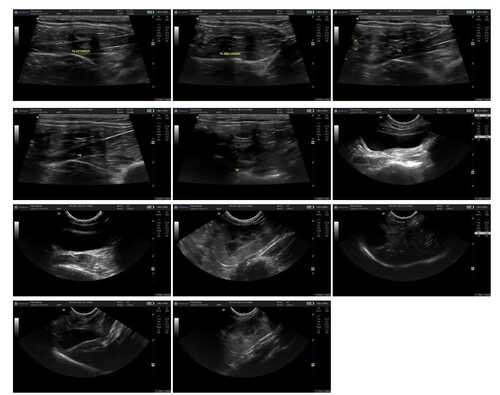

Oi, pessoal! Eu sou o Tico e nasci um gato pirata e criptorquidio. Nasci com um olhinho só funcionando e com as bolinhas ectopicas no abdômen. E agora preciso fazer duas cirurgias muito importantes pra melhorar minha qualidade de vida: castração testicular ectópica abdominal e enucleação para retirar o meu olhinho. Por serem duas cirurgias de risco, os custos são um pouco mais alto que o normal, quem puder ajudar com um pouquinho, ou compartilhando para mais pessoas, me deixaria muitoooo agradecido!

(Essa vakinha é para angariar fundos para poder realizar essas 2 cirurgias, e eu poder me tornar um gatinho pirata e saudável, dessa vez caolho e sem problemas nas bolinhas :)